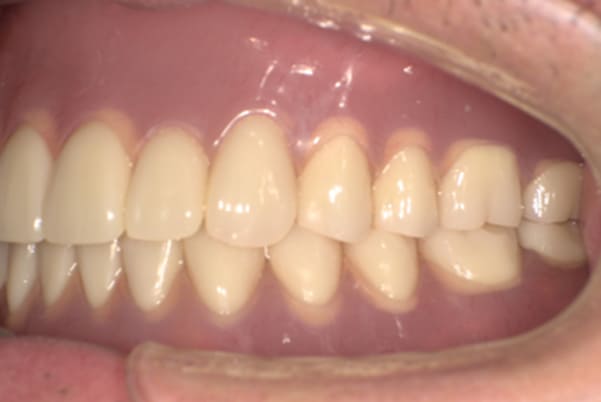

症例レポート[CASE.07]

子供の結婚式で恥ずかしくないようにしたい

- 男性(50代)

- 食べれない、歯がぐらつく、子供の結婚式で恥ずかしくないようにしたい、歌いたい

- 上顎精密金属床総入れ歯

- 下顎精密金属床総入れ歯

- 磁性アタッチメント(白金加金) 3歯

- 上顎精密金属床総入れ歯:55万円

- 下顎精密金属床総入れ歯:55万円

- 磁性アタッチメント:11万円×3歯

(白金加金)

合計:143万円(税込)

歯周炎により歯が多く抜けた状態で咬めるところがほとんどない状態でした。

検査の結果、上の歯3本は何とか残せる状態で、ご本人もできるだけ歯は抜きたくないとのご希望であったため、残せる歯もそのままバネをかけると負担が大きく数年で抜歯となる可能性が高いため、ご自身の歯に磁石を装着することで歯を長持ちさせ、入れ歯も外れにくい入れ歯にしました。

ご自身の歯を抜かず、磁石を装着することで、歯への負担を減らし、入れ歯も外れないような設計としました。

プラスチックの入れ歯は、強度がないため厚くなり違和感がでやすいこと、熱を通しにくく食べ物の熱が伝わりにくい、壊れることがあることが欠点のため、患者様の生活習慣やご希望をお聞きし、上顎には金属を用いることで、プラスチックの1/3程度の厚みとなり、温かい食べ物や冷たい食べものの熱をお口で感じ、丈夫な入れ歯の設計としました。

上顎に金属は用いていますが、外観に触れないため、機能性と審美性を持ち合わせた自然な口元になりました。